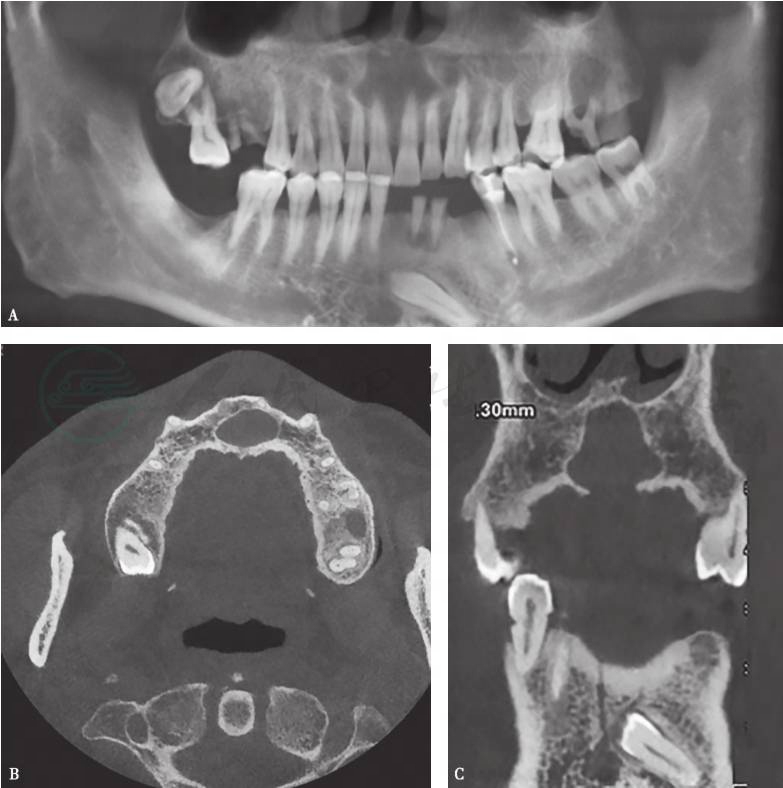

囊肿呈类圆形低密度影,位于切牙管部位,常延伸入双侧中切牙之间。边缘清楚光滑,周围有骨质硬化带。伴发感染时,病变边缘多不清楚,周围硬化带常不连续(图1)。

图1鼻腭囊肿

上颌骨CBCT,A.CBCT全景重建图;B.CBCT横断位;C.CBCT冠状位。示上颌切牙管异常扩大,呈类圆形囊腔,边缘清楚,周围见骨白线包绕